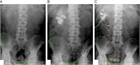

1. 片側の腰背部痛や側腹部痛では水腎症を念頭に置き、まず超音波検査を行い、尿路閉塞の位置と原因を同定するには単純CTを撮影する。